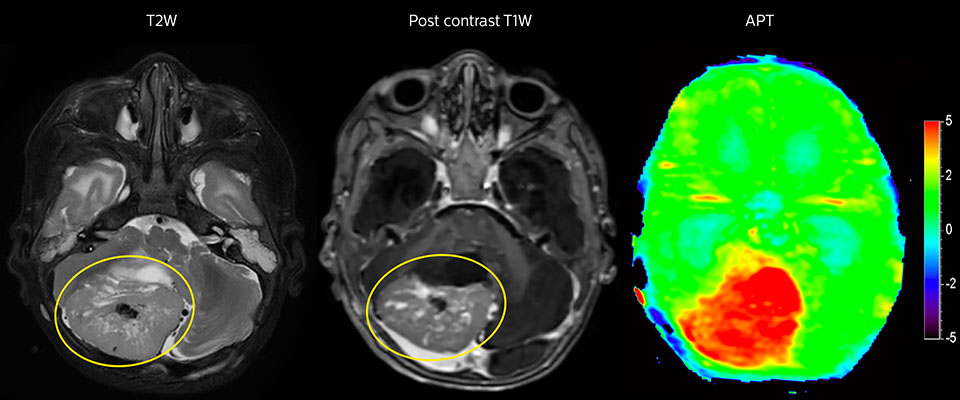

Tumor evaluation in a 1-year-old child with medulloblastoma. This aggressive tumor type is very solid and homogeneous. The high APT signal corresponds with the post-contrast image of this high-grade tumor.